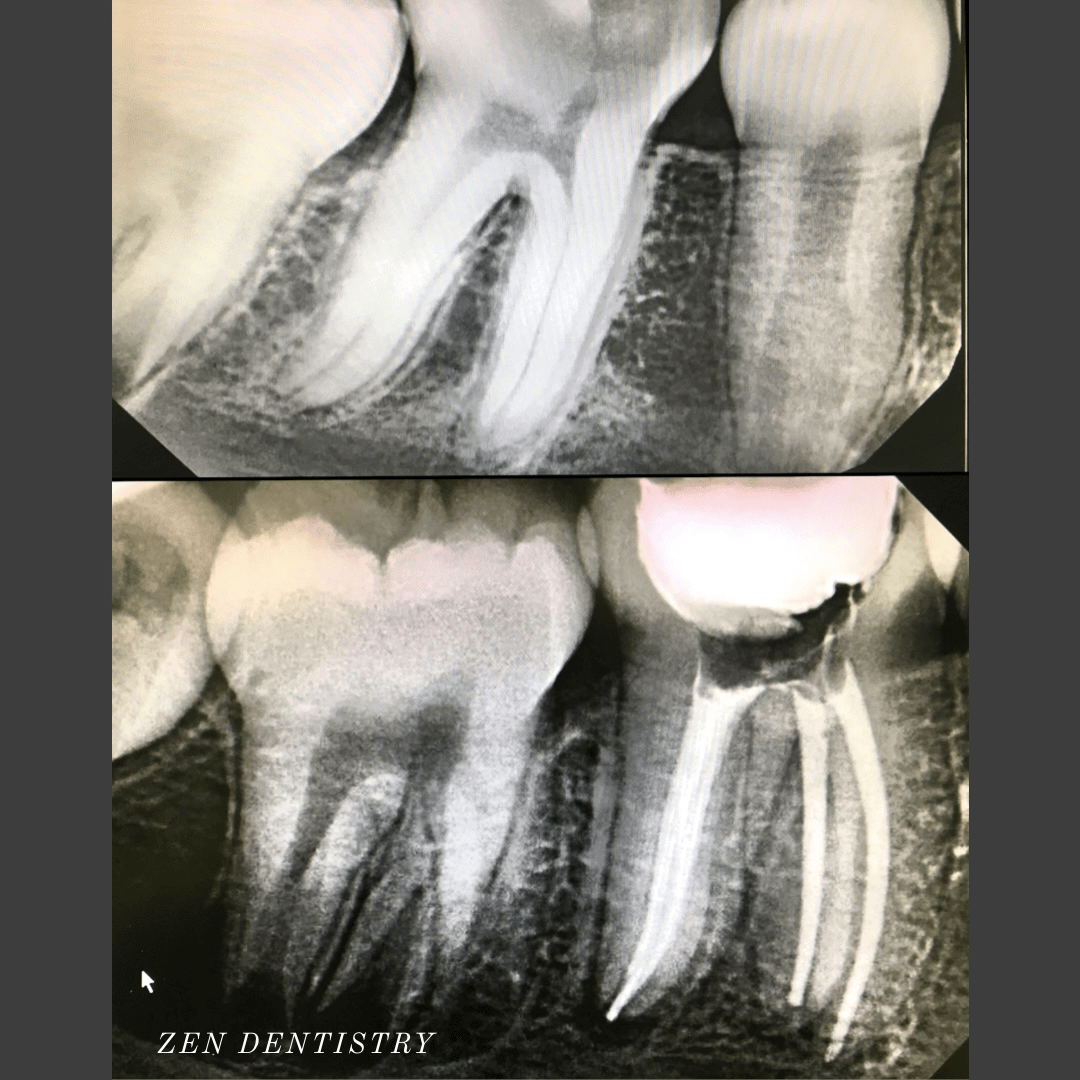

Patient presented to the A thorough clinical exam, endodontic screening and proper x rays led to the diagnosis of irreversible pulpitis(inflamed pulp tissue) due to secondary dental caries with inflamed periodontal ligaments.